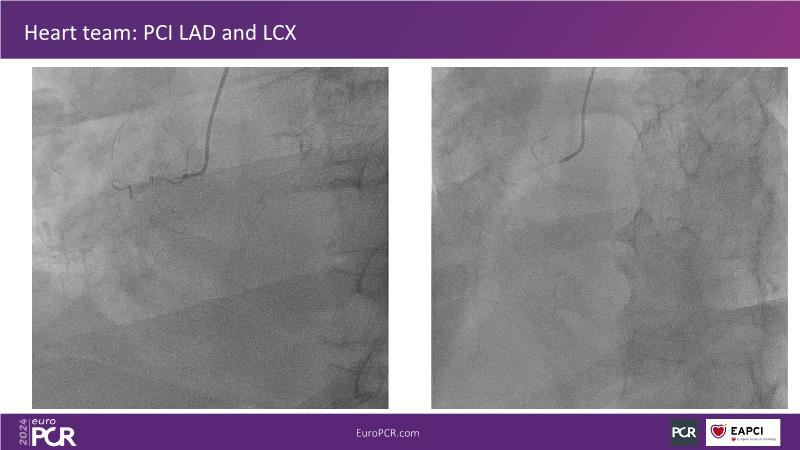

Tune in to this session to discover how reducing reliance on contrast opacification enhances procedural safety and enables more thorough revascularization in complex PCI scenarios. Learn that ultra-low contrast (ULC) PCI encompasses various interventional skills and specialized tools, many already familiar to interventional cardiologists. Embrace a mindset shift, starting with applying ULC PCI principles in simple cases and progressing to complex interventions.

- To learn specific ways of using intra-coronary imaging and physiology, as well as dedicated tools like Dynamic Coronary Roadmap, to perform PCI without contrast administration

- To share the principles of PCI through recorded cases to better understand how they work in practice